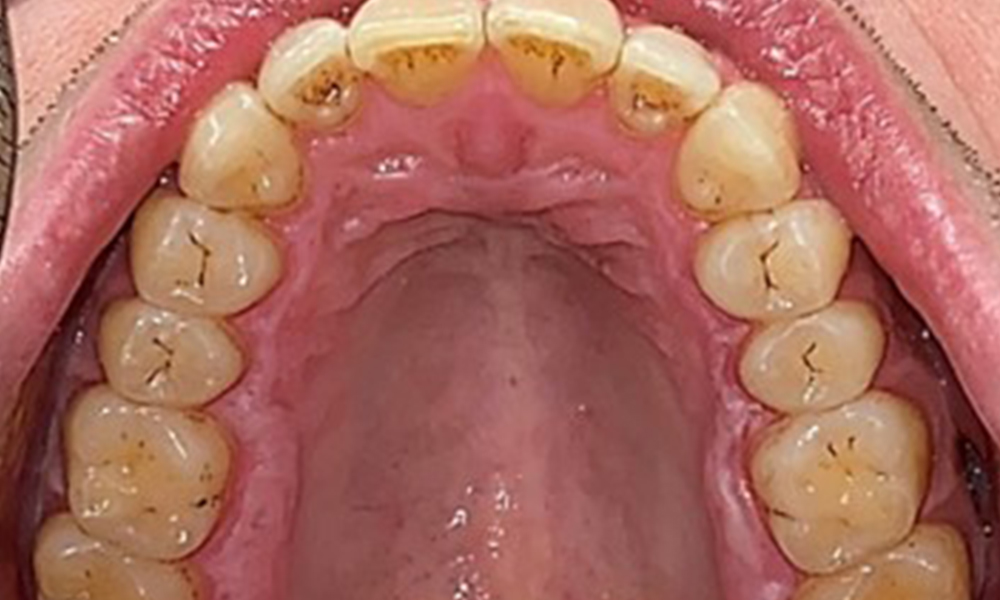

The patient has full dentition with a total of 28 teeth. There were noteworthy erosions and attritions. (Fig. 4, Fig. 5). Due to bruxism, the patient has been wearing a splint with an adjusted bite block at night for many years. The erosions were caused by long-term consumption of isotonic beverages. No periodontal bone loss or active caries were observed.